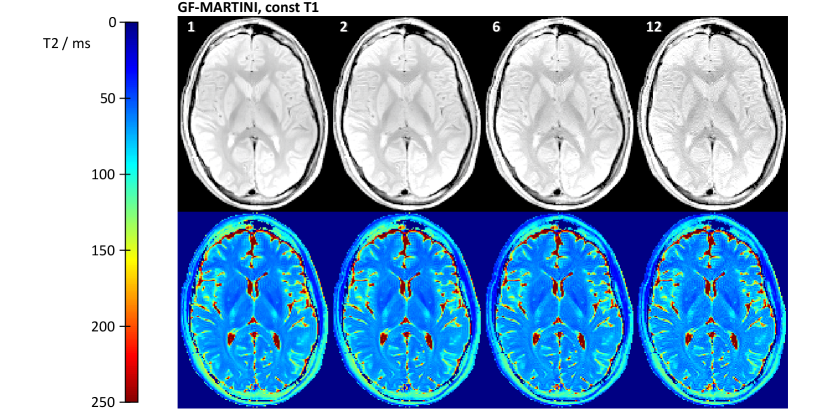

The mean T2 values obtained by GF-MARTINI are in remarkably good agreement with the fully sampled reference and very stable for all undersampling factors. Moreover, Fig. 7

depicts reconstructions of the same data with the assumption of a constant T1 for all pixels. It turns out that the GF-MARTINI reconstructions with constant T1 are almost indistinguishable from the results obtained with a full T1 map. The ROI analysis in Table III confirms this observation as all measurable deviations between the two GF-MARTINI versions remain within .